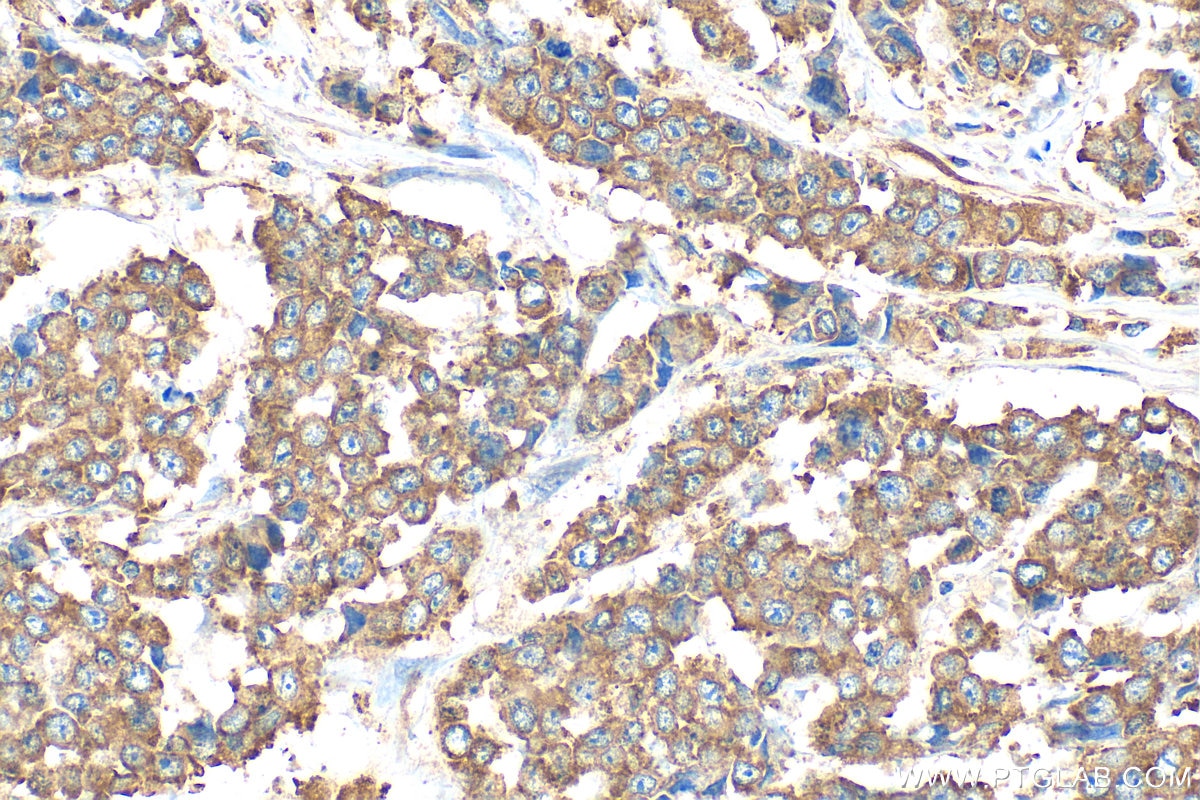

25799-1-AP targets PLA2G12B in WB, ELISA applications and shows reactivity with human, mouse, rat samples.

| Full Name | phospholipase A2, group XIIB |

| Gene Symbol | PLA2G12B |

Phospholipase A2 (PLA2) enzymes catalyze hydrolysis of glycolipids to release free fatty acids and lysophospholipids. PLA2G12B is a secreted group XIIB secretory phospholipase A2-like protein belonging to the PLA2 family, but it is catalytically inactive due to an amino acid change in its active site and has altered phospholipid-binding properties (PMID: 14516201). It is located outside the cell membranes and strongly expressed in liver, small intestine and kidney, and recently reports revealed that Pla2g12b gene may be implicated in HDL cholesterol levels and metabolism (PMID: 22912808). The calculated molecular weight of PLA2G12B is 21 kDa.